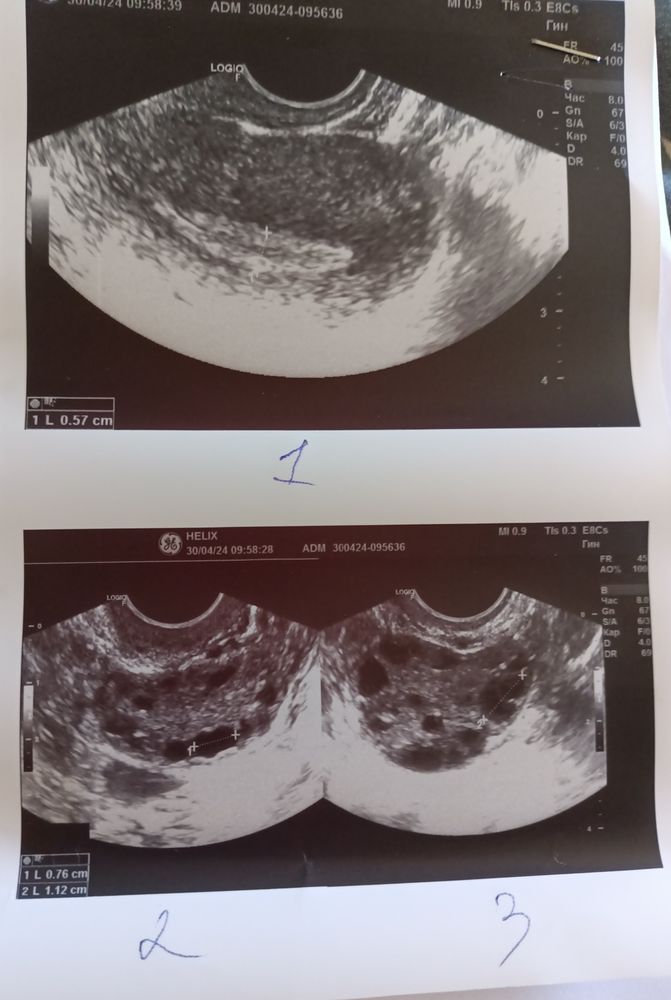

Добрый день. Сходила на фолликулометрию всё не очень, что и следовало ожидать, день цикла 19, доминантного фолликула нет, жёлтого тела нет, эндометрий тонкий. Собственно ничего удивительного, расстроена, но да ладно.